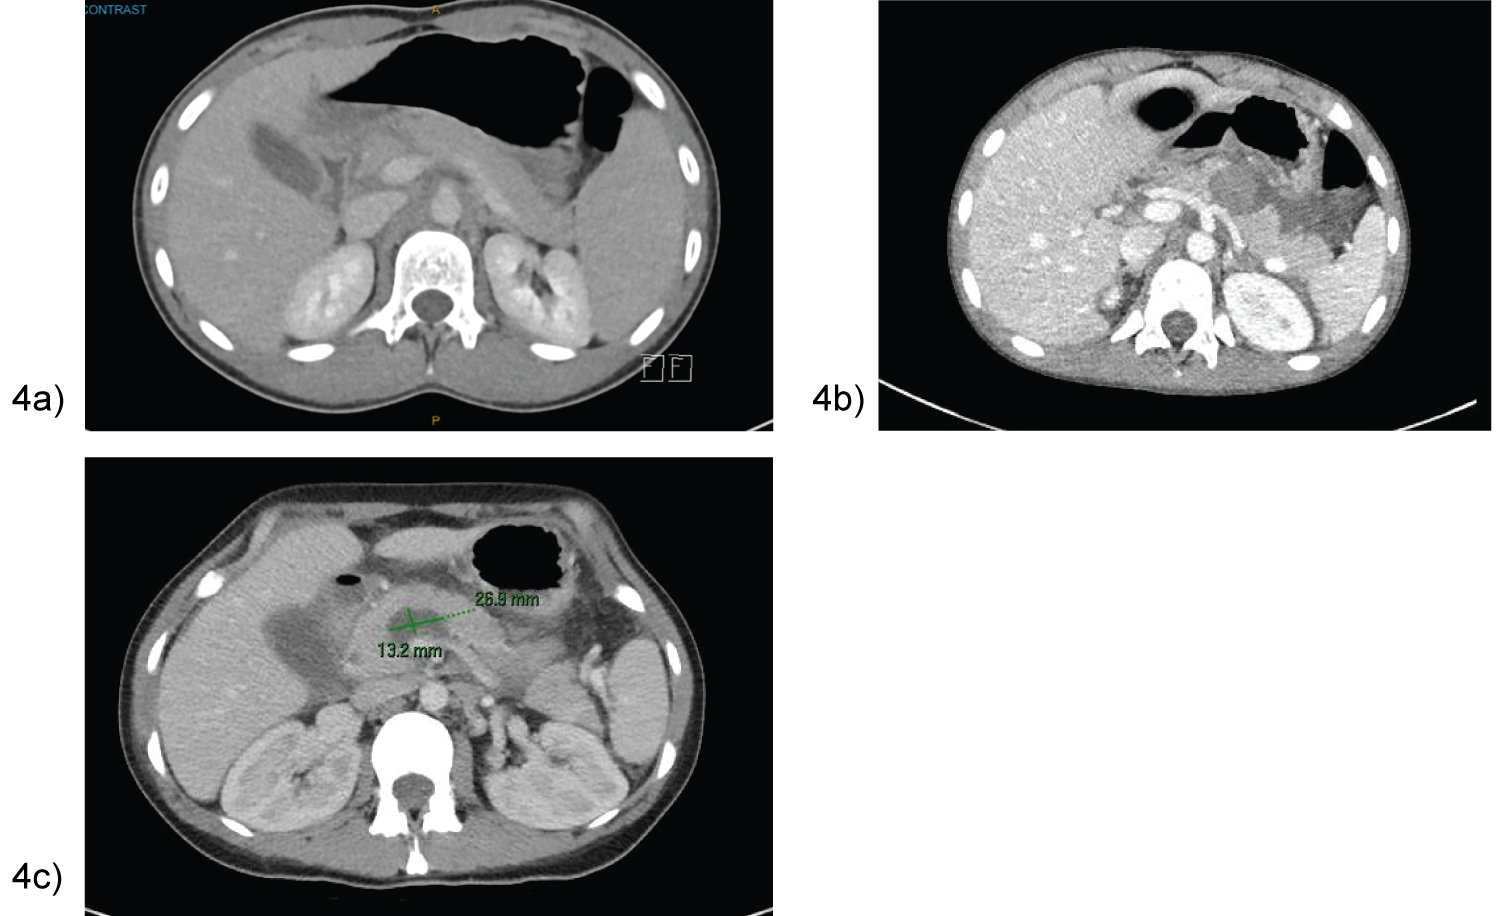

All 7 patients included in this series were well with no comorbidities or previous abdominal surgery; and haemodynamically stable at time of injury. Table 1 is a summary of their clinicopathological characteristics. The average age was 14 (age range 5-34 years), with majority of patients being female. Acute traumatic pancreatitis was confirmed with an elevated lipase ranging from 1700-12385 U/L, as well as a computed tomography (CT) showing an AAST Grade IV pancreatic neck transection (Figure 4). Case 4 and 5 also had additional organ injuries; ranging from grade I-II splenic and liver lacerations respectively.

Figure 4: Control cerebral angiography showing embolized AVM, and flow - related aneurysm. View Figure 4